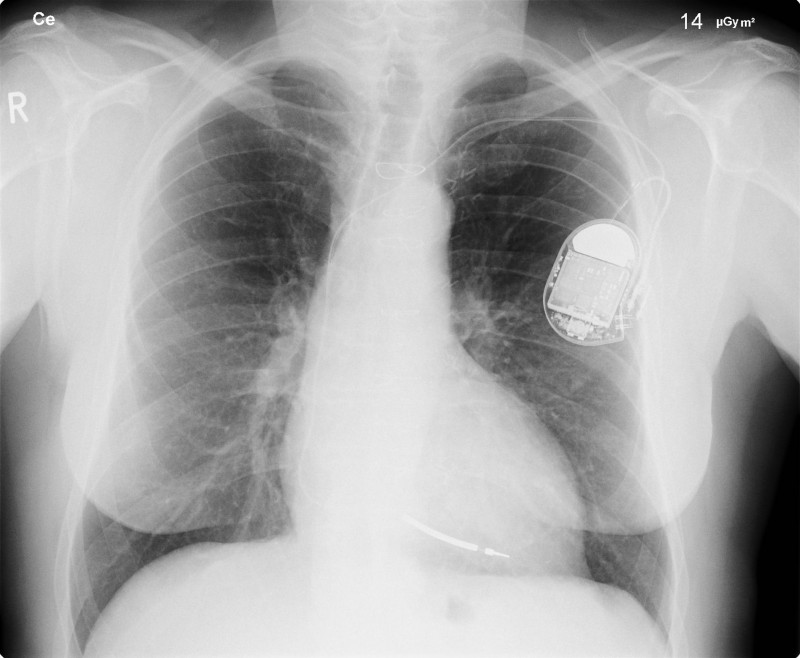

The most common x-ray images are simple shadows. Since x-ray photons have high energies, they penetrate materials that are opaque to visible light. The more energy an x-ray photon has, the more material it will penetrate. So an x-ray tube may be operated at 50.0 kV for a chest x ray, whereas it may need to be operated at 100 kV to examine a broken leg in a cast. The depth of penetration is related to the density of the material as well as to the energy of the photon. The denser the material, the fewer x-ray photons get through and the darker the shadow.

Thus x rays excel at detecting breaks in bones and in imaging other physiological structures, such as some tumors, that differ in density from surrounding material. Because of their high photon energy, x rays produce significant ionization in materials and damage cells in biological organisms. Modern uses minimize exposure to the patient and eliminate exposure to others. Biological effects of x rays will be explored in the next tutorial along with other types of ionizing radiation such as those produced by nuclei.

Breast cancer is the second-leading cause of death among women worldwide. Early detection can be very effective, hence the importance of x-ray diagnostics. A mammogram cannot diagnose a malignant tumor, only give evidence of a lump or region of increased density within the breast. X-ray absorption by different types of soft tissue is very similar, so contrast is difficult; this is especially true for younger women, who typically have denser breasts. For older women who are at greater risk of developing breast cancer, the presence of more fat in the breast gives the lump or tumor more contrast. MRI (Magnetic resonance imaging) has recently been used as a supplement to conventional x rays to improve detection and eliminate false positives. The subject’s radiation dose from x rays will be treated in a later tutorial.